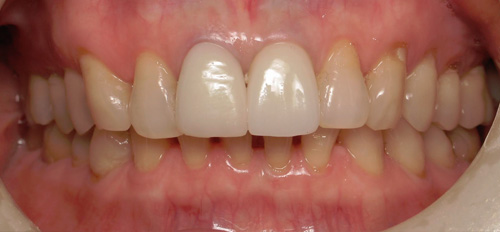

Smile Gallery